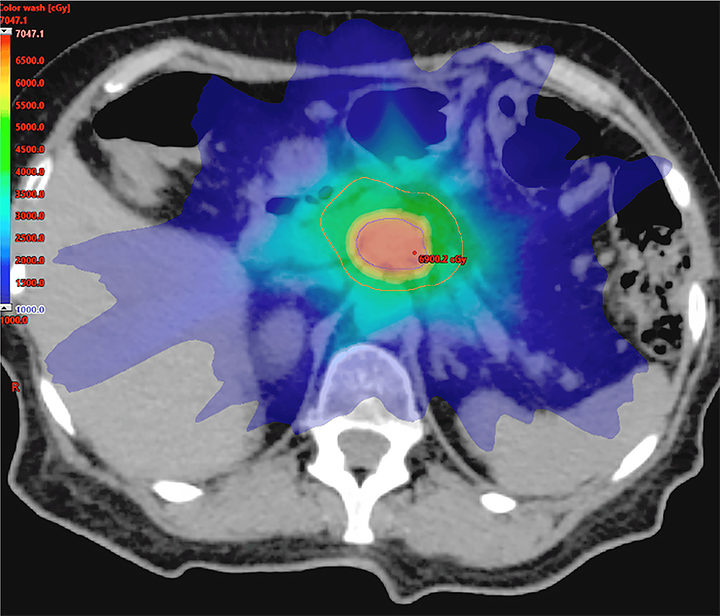

External beam radiation therapy for pancreatic cancer

External beam radiation therapy uses imaging to precisely target the tumor, concentrating treatment to cancer cells.

Radiation therapy plays a crucial role in the multidisciplinary management of pancreatic cancer. It involves the use of high-energy X-rays or other forms of radiation to target and destroy cancer cells. Radiation therapy can be administered before surgery (neoadjuvant), after surgery (adjuvant), or in combination with chemotherapy (chemoradiation) to enhance the treatment’s effectiveness.

External beam radiation therapy is delivered from a machine that moves around that patient while laying down. As it rotates, it directs radiation to specific points predetermined by the radiation oncologist, maximizing the dose to the cancer while avoiding healthy tissues and structures. Radiation can be delivered in a single dose or over several weeks, depending on the treatment plan.